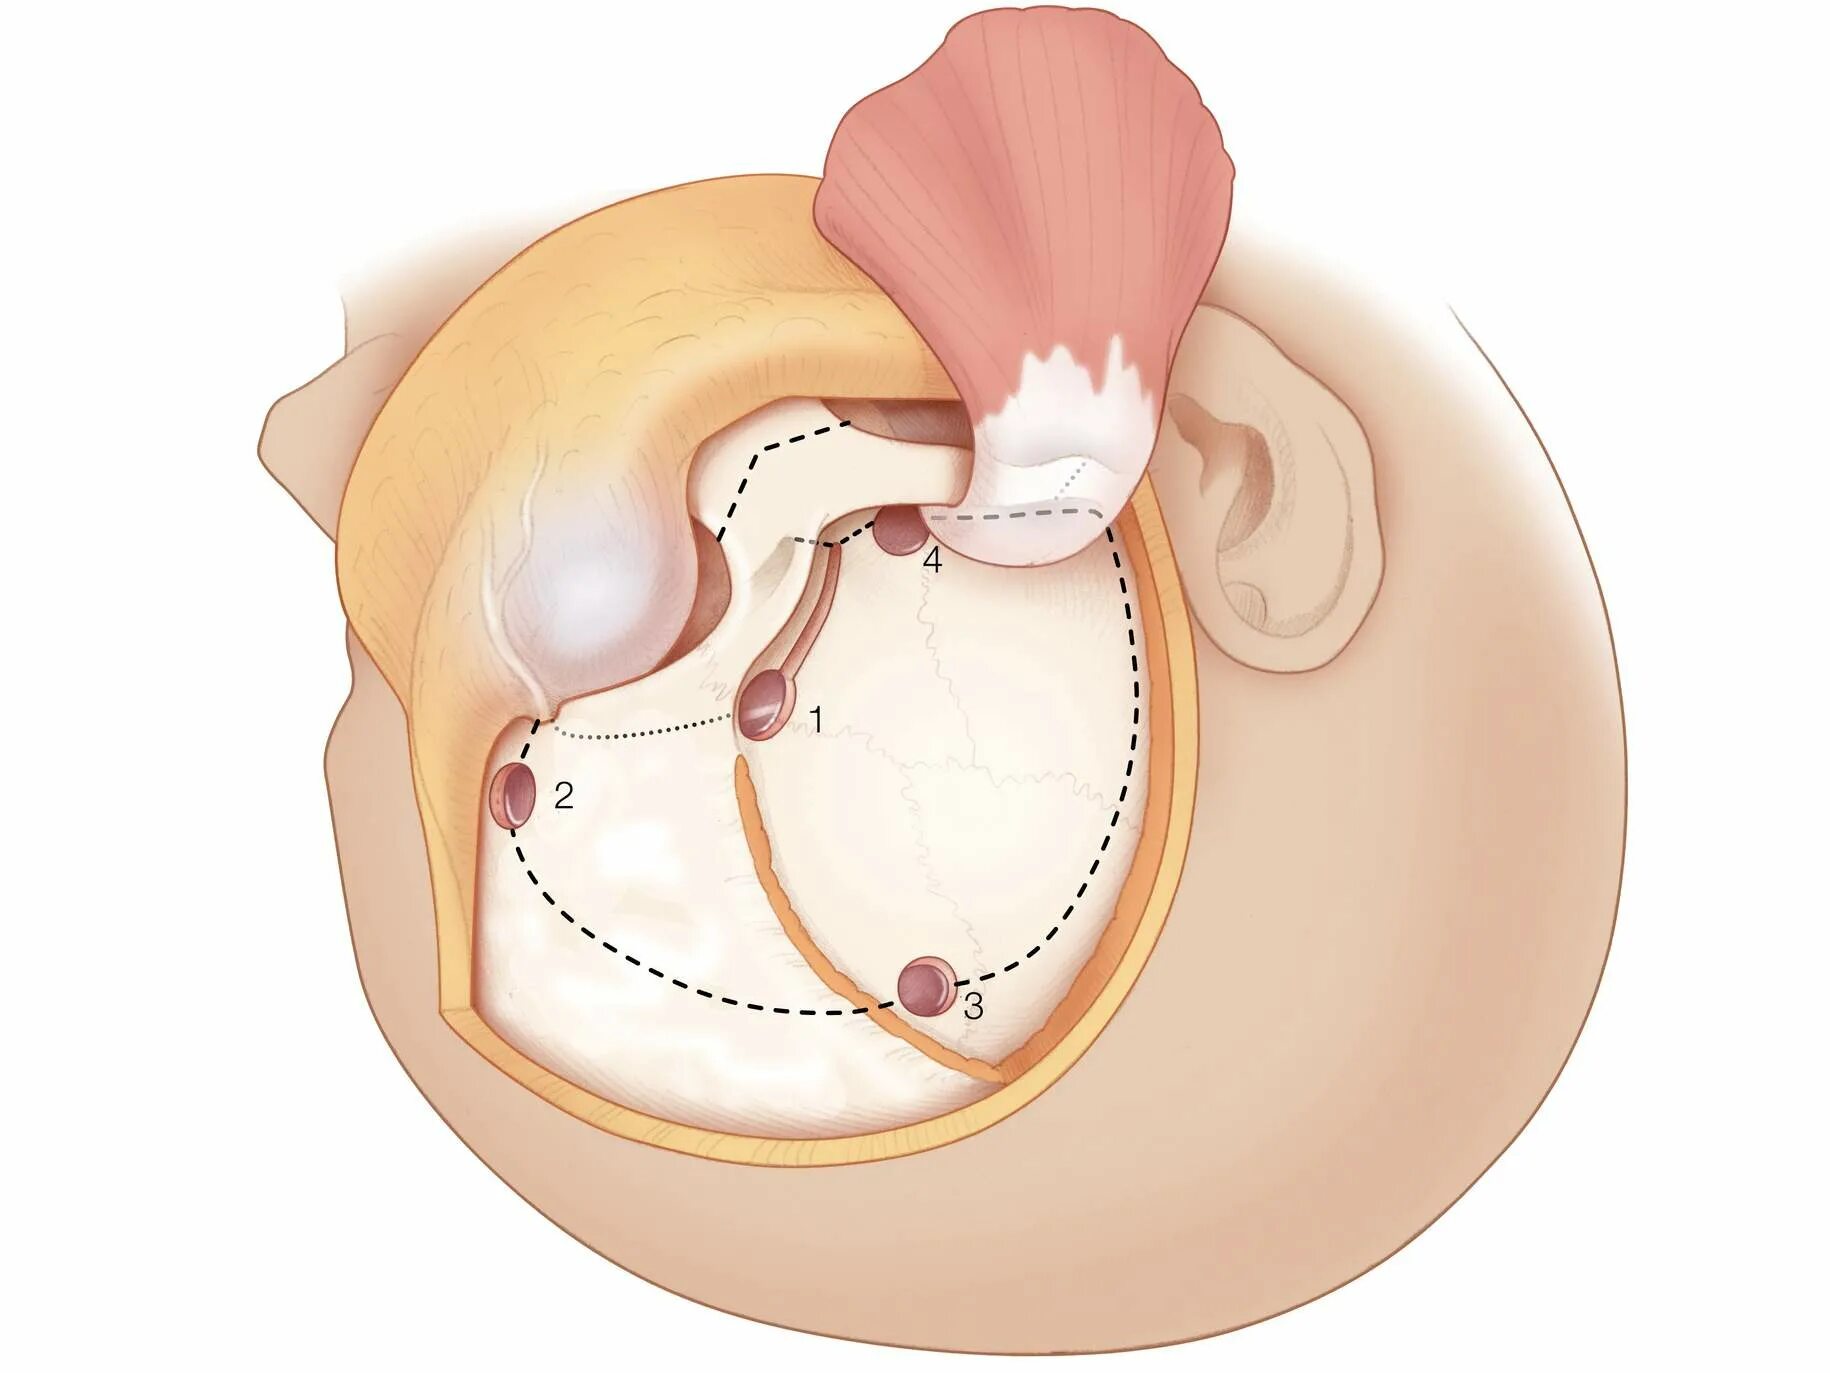

Спинка турецкого седла